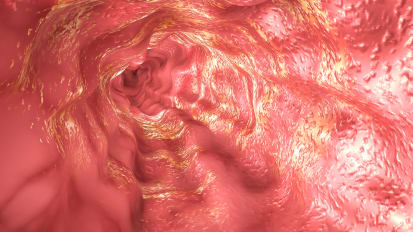

Johns Hopkins Developing New Test for Esophageal Cancer

A Johns Hopkins gastroenterologist and a team of researchers use specific genetic biomarkers to detect dangerous changes in the cells that line the inside of the esophagus. 3D image shows concept model of esophageal cancer.